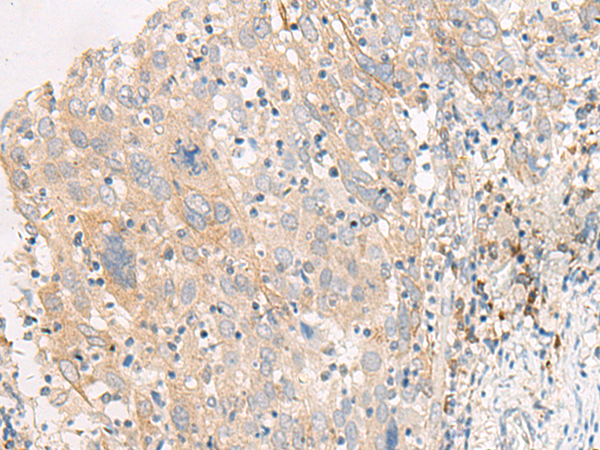

ELISA, IHC |

IHC positive control: |

Human cervical cancer |

IHC Recommend dilution: |

25-100 |